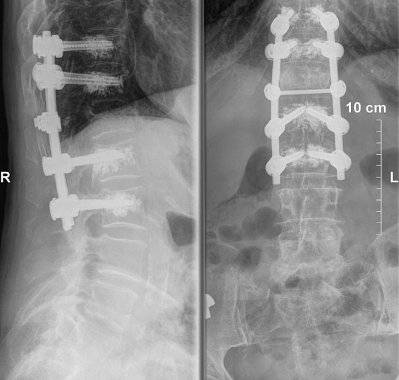

Do wykonywanych zabiegów w zakresie kręgosłupa należy zaliczyć też zabiegi resekcji trzonów i implantów trzonów kręgów w odcinku lędźwiowym kręgosłupa. Ponadto podejmuję się leczenia powikłań osteoporozy kręgosłupa. Moja oferta to również stabilizacja tylna, międzywyrostkowa w dyskopatii lędźwiowej i zespole po nukleotomii.

- stabilizacje transpedicularne i implanty międzytrzonowe PLIF Plivios ,

- stabilizacja kręgosłupa lędźwiowo-krzyżowo-biodrowa,

- stabilizacja transpedicularna przy złamaniu kręgosłupa lędźwiowego,

- stabilizacja kręgosłupa z wykorzystaniem śrub kaniulowanych,

- stabilizacja złącza piersiowo-lędźwiowego,